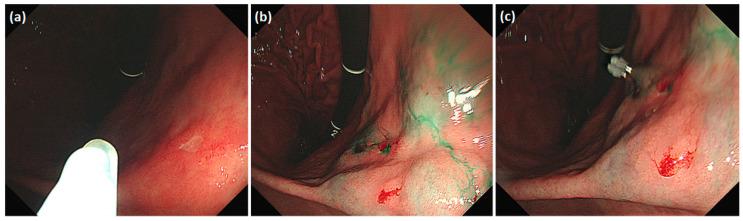

Near-infrared (NIR) fluorescence lymphography-guided minimally invasive gastrectomy using indocyanine green (ICG) is employed to visualize draining lymphatic vessels and lymph nodes. Endoscopically injected ICG spreads along the gastric wall and emits fluorescence from the serosal surface of the stomach. We aimed to assess the efficacy of ICG diffusion in securing the resection margin. We retrospectively analyzed 503 patients with early gastric cancer located in the body of the stomach who underwent fluorescence lymphography-guided gastrectomy from 2018 to 2021. One day before surgery, ICG was endoscopically injected into four points of the submucosal layer peritumorally. We measured the extent of resection and the resection line based on the ICG diffusion area from the specimen using NIR imaging. The mean area of the ICG diffusion was 82.7 × 75.3 and 86.7 × 80.2 mm2 on the mucosal and serosal sides, respectively. After subtotal gastrectomy, the length of the proximal resection margin was 38.1 ± 20.1, 33.4 ± 22.2, and 28.7 ± 17.2 mm in gastroduodenostomy, loop gastrojejunostomy, and Roux-en-Y gastrojejunostomy, respectively. The ICG diffusion area along the gastric wall secured a resection margin of >28 mm. The ICG diffusion range can be used as a simple and easy method for determining the resection margin during gastrectomy using NIR imaging.